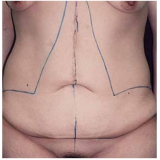

Abdominoplastia com Lipo

Há momentos em que é necessário ter por perto profissionais qualificados e dedicados à pronta recuperação do paciente. A FF Cirurgia Plástica oferece e coloca à sua disposição o que existe de mais atualizado em procedimento cirúrgico para abdominoplastia com lipo. Com o objetivo de levar qualidade à vida dos clientes, a instituição oferece infraestrutura adequada às necessidades de cada um: cuidado médico humanizado, realizado através de dedicação, profissionalismo e amor.

Você precisa de um consultório médico que realize abdominoplastia com lipo com segurança!